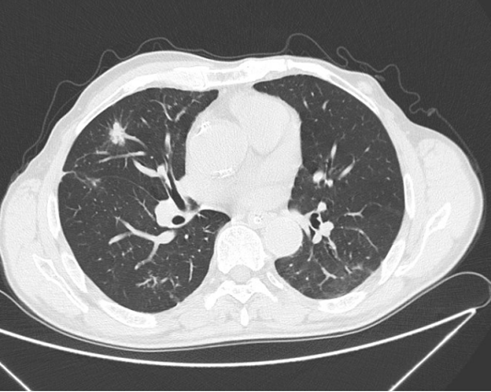

付大爷的情况特殊,CT检查显示其右肺中叶不规则结节影较前增大,PET-CT检查提示糖代谢异常增高,考虑为恶性结节。同时,右肺下叶前基底段及后基底段也发现混杂密度结节。然而,由于付大爷的长期气管切开状态和舌癌术后咽后壁组织松软堵塞原声门上气道开口的情况,使得常规的胸外科全身麻醉——经口置入双腔支气管插管,术中单肺通气的方法难以实施。

面对这一挑战,泰达医院的麻醉科、放射科、ICU以及护理部进行了充分的多学科术前讨论(MDT)。放射科主任经阅读胸部CT以及PET-CT后考虑右肺中叶为恶性可能性大,右肺下叶结节为良性病变可能性大。麻醉科马浩南主任带领团队术前与胸外科医师多次沟通手术细节,充分评估患者气道情况:认为患者舌癌术后,口腔及声门上解剖异常,存在声门狭窄,传统经口双腔支气管插管难以成功,且可能对患者造成医源性损伤甚至气管撕裂风险;通过颈胸部CT以及气管镜检查,发现患者的气管造口以下无气道狭窄,并通过影像学资料计算可置入单腔气管导管。故设计麻醉方案为经气切造口置入单腔加强型气管插管+支气管封堵器。但因封堵器在摆放体位和手术操作时位置容易移位,定位要求高于传统双腔管。经麻醉团队讨论,决定使用可视单腔气管插管实时监测封堵器套囊位置。经与胸外科李林主任沟通后认为方案可行,如期手术。